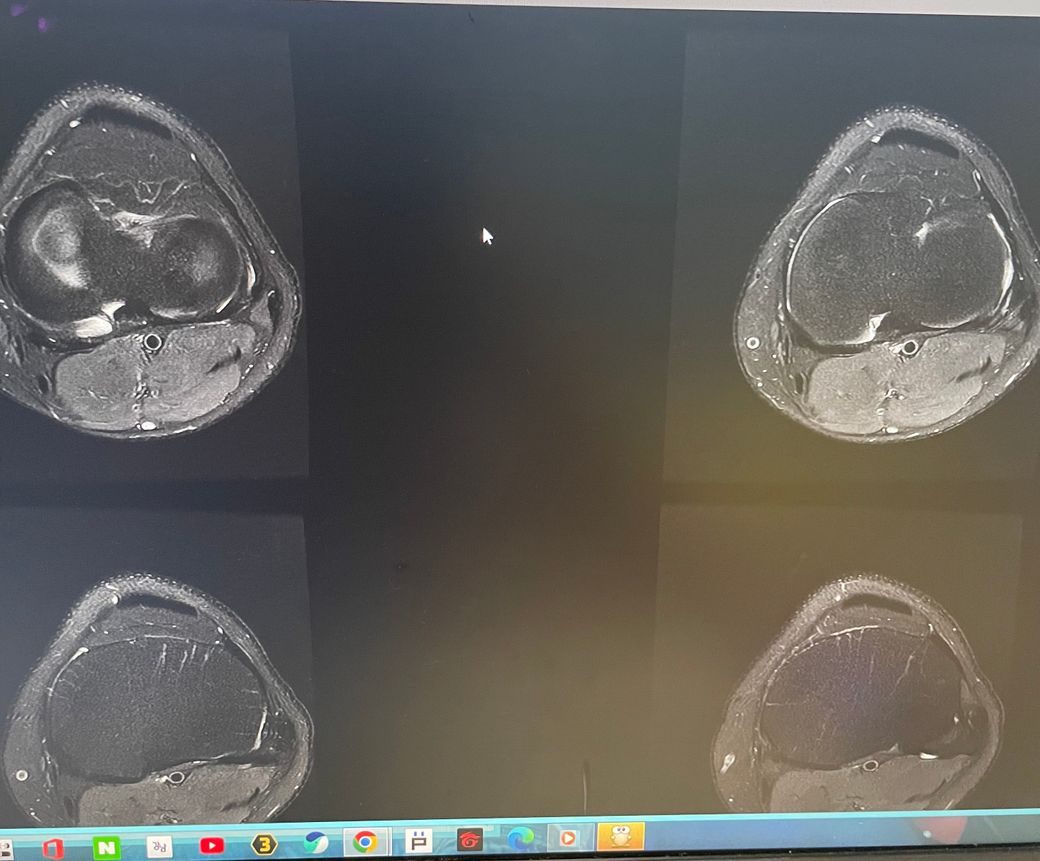

무릎 왼쪽 mri 사진 판독 부탁드리겠습니다.

안녕하세요 3달전쯤에 무릎을 다쳐서 약 한달전에 mri를 찍었습니다.

현재 판독상 인대나 반월연골 손상은 없는 것으로 판독지에 기재되어 있습니다. 임상적인 증상도 중요하니 담당의사와 상의하시고 신검시에 해당과 군의관 판정을 받으시는 것이 좋겠습니다.

십자인대에는 문제가 없지만 반월판의 문제가 있는 것으로 보입니다.

ACL 즉 전방 십자 인대에 불규칙한 소견은 있으나 Tear 즉 십자 인대가 파열되었다는

소견은 관찰되지 않는 상태이며 연골에 퇴행성 변화는 있는 것으로 보이나 이 역시 R/O

으로 확실하지 않음을 의미합니다. 결과적으로 십자 인대의 파열이 명확하지 않는 상태로

군대를 연기할 사유가 될지는 모르며 전방 십자 등 인대 손상의 경우는 명확하게 파열된

소견을 보이지 않는 경우, 군 입대에 문제가 되지는 않을 것으로 생각됩니다.